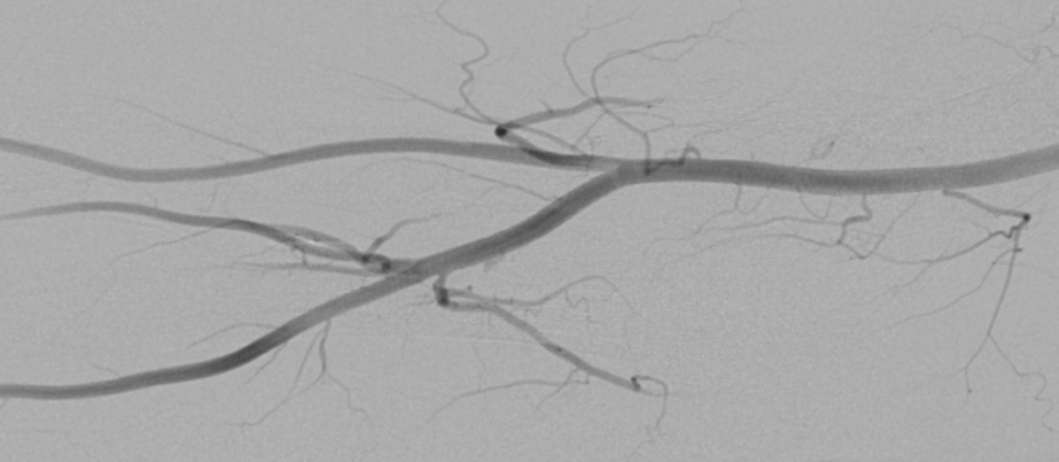

桡动脉位于肱桡腱和桡侧腕屈肌腱之间,从腕部到远端桡骨头有2cm可以触及搏动。初始穿刺部位尽可能在远端,但至少在茎突近端1cm,以避免穿刺屈肌支持带( retinaculum flexorum )和桡动脉小的表浅分支。但任何病人必须有手的双重动脉供血才是经桡动脉路径的适应症。

桡动脉直径![]() 桡动脉解剖分型![]() 桡动脉解剖及其意义

位置表浅:搏动易于触及和穿刺

管径较细:男,2.7±0.4;女,2.4±0.4

血管壁α1肾上腺素能受体分布多:刺激痉挛

走行变异多,迂曲,分支多:血管损伤及出血基础